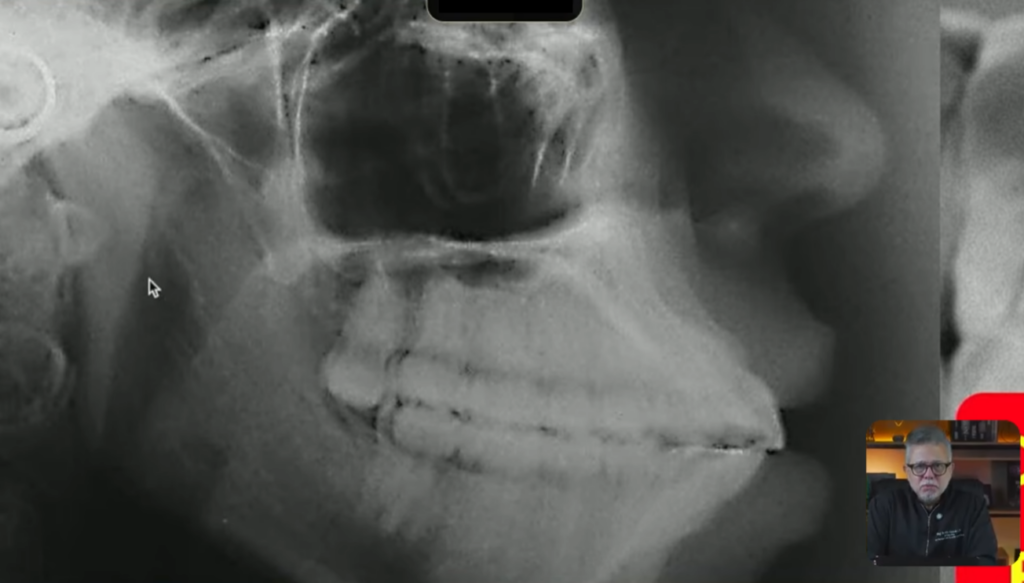

Todo mundo aqui consegue ver bonitinho que os incisivos tanto superiores quanto inferiores, eles estão inclinados para vestibular:

Minha paciente nesse caso não consegue nem fechar a boca direitinho aqui, vocês estão conseguindo ver isso?

Então nós estamos diante de uma paciente biprotrusa com incisivos inclinados para vestibular